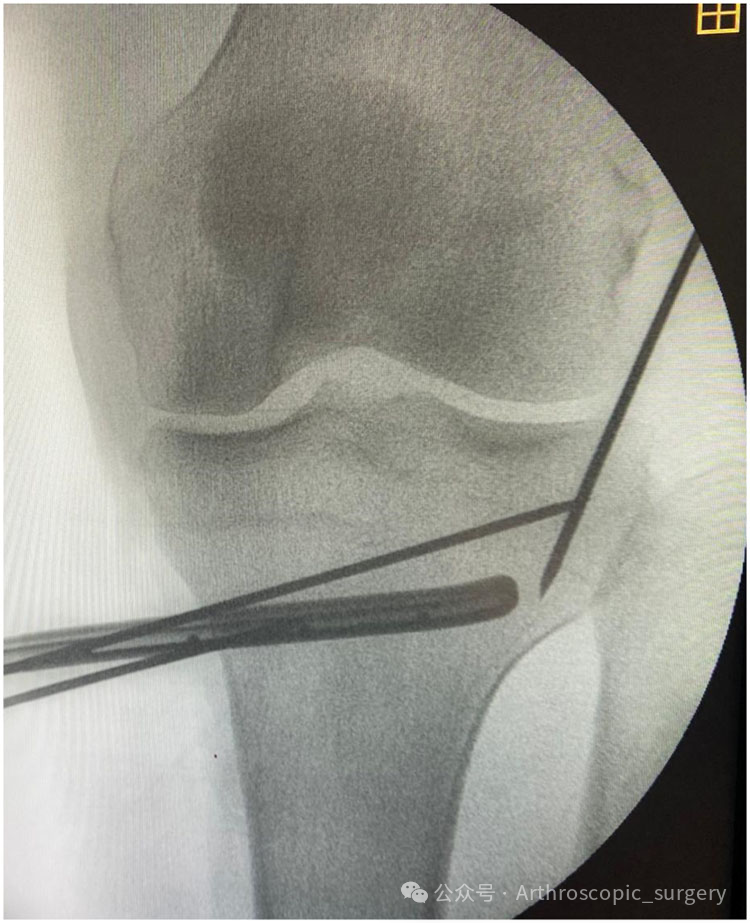

Anteroposterior fluoroscopic image of the left knee demonstrating the osteotomy wire ending at the level of the proximal third of the fibular head in the axial plane and to the level of the hinge wire in the coronal plane.